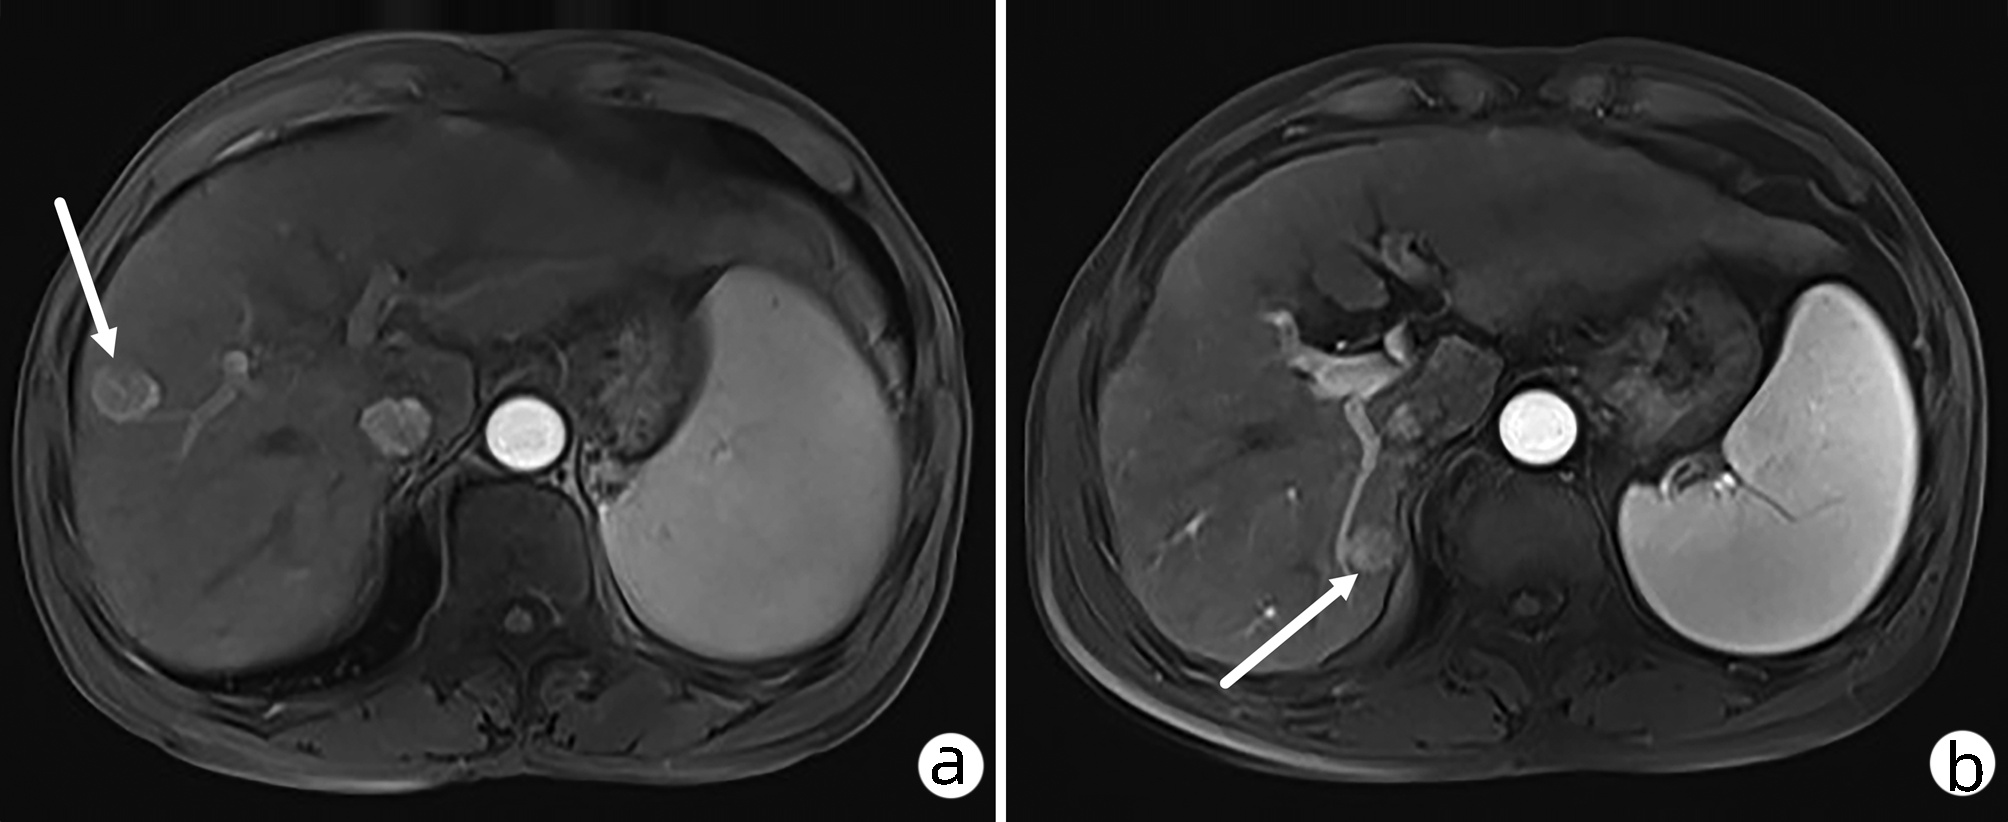

Hepatocellular carcinoma with bile duct tumor thrombus: A case report

Renjie LU, Fangfang SUN, Jie DU, Lirong ZHAO

2022, 38(8): 1872-1874. DOI: 10.3969/j.issn.1001-5256.2022.08.028

Abstract(762) HTML (437) PDF (3665KB)(68)

Abstract: